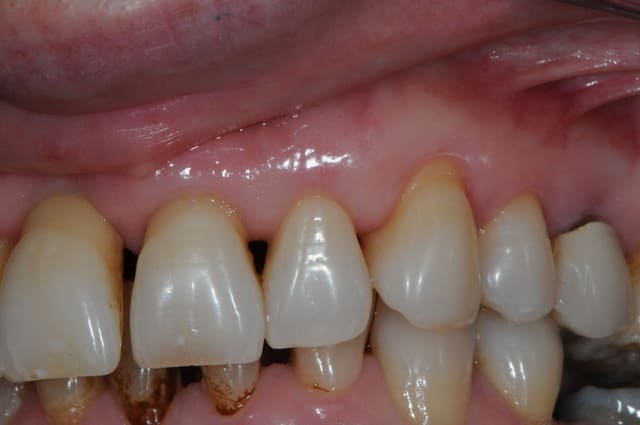

patiente 43 ans, très souriante, rigole tous le temps, fumeuse devant l'Eternel (1paquet/jour).

la parodontite et la mobilité sur 12 l'inquiète d'autan plus que les dents sont de plus en plus mobiles.

la 12 est perdue, mais également la 11 qui subit déjà une forte résorption gingivale.

21 et 22 pas beaucoup mieux.